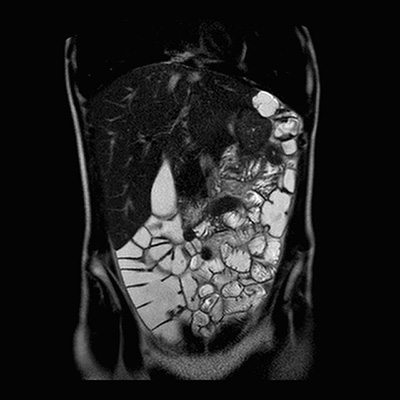

Gracias a los campos de visión amplios de las nuevas resonancias, y a secuencias de tiempo de adquisición rápidas, la resonancia se ha convertido en una buena herramienta para el estudio del aparato digestivo, muy útil en enfermedades como el Síndrome de Crohn.

Ejemplos